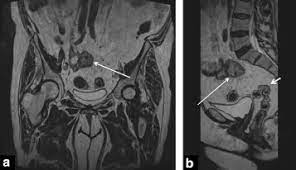

Pdf Descending Colon Endometriosis Misdiagnosed As Diverticulitis A Case Report from i1.rgstatic.net Ovarian cancer can attach to the intestinal tract, causing symptoms that mimic irritable bowel syndrome (ibs). Another condition that can be misdiagnosed as cancer in the colon is hemorrhoids. A diagnosis of acute diverticulitis can often be made by the history, demographics, and physical exam alone. When looking at endometriosis versus ovarian cancer, it is clear to see that some symptoms are shared by the two. This could be because the cancer has spread to the colon or because pressure from fluid buildup could be affecting the area. Patients can help prevent diverticulitis and cancer from eating a diet rich in fiber, drinking enough water, and exercising regularly. This is primarily because endometriosis is a complex disorder that can often mask itself as other conditions (due to its similar symptoms as seen in said disorders). I had a full hysterectomy on december 12 th, and ovarian cancer stage 3 , serous, was confirmed.